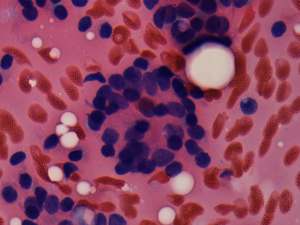

Aspiration cytology resulted in benign, colloid goiter.

Surgery was performed because of cosmetic reasons. Histopathology disclosed benign hyperplastic nodular goiter.